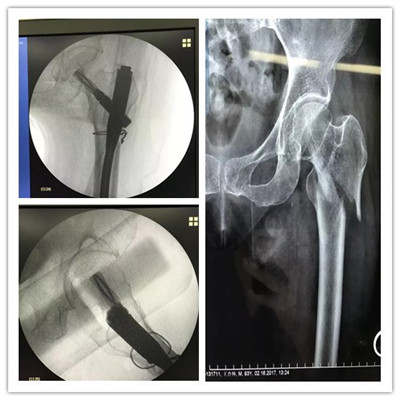

近日,舟山廣安骨傷醫(yī)院成功為一位95歲高齡的老太太實(shí)施股骨粗隆骨折微創(chuàng)手術(shù)。術(shù)后一天就可以床上活動(dòng)。

老太太今年已經(jīng)95歲高齡了,一周前在家不慎滑倒摔傷,疼痛難忍,不敢活動(dòng),遂由家人急送至舟山廣安骨傷醫(yī)院,經(jīng)拍片檢查確診為左股骨粗隆粉碎性骨折。

廣安醫(yī)院關(guān)節(jié)科副主任羅軍稱,老太太不但高齡,還患有心臟病,低蛋白血癥,重度骨質(zhì)疏松癥,手術(shù)麻醉風(fēng)險(xiǎn)極高,但若保守治療需要長(zhǎng)期臥床,且不說骨折能否愈合,致命的臥床并發(fā)癥就極難避免。經(jīng)過醫(yī)院多科室會(huì)診,在腰部麻醉下,羅軍副主任為老太太實(shí)施了股骨髓內(nèi)釘(PFNA)微創(chuàng)手術(shù)。術(shù)后各項(xiàng)生命體征平穩(wěn),術(shù)后第一天就可床上活動(dòng),目前可以持助行器下地活動(dòng)了。